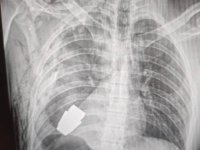

Вперше на Волині: лікарі замінили клапан серця без розрізу грудної клітки. ФОТО

Лікарі замінили аортальний клапан без зупинки серця через 3-х сантиметровий розріз.